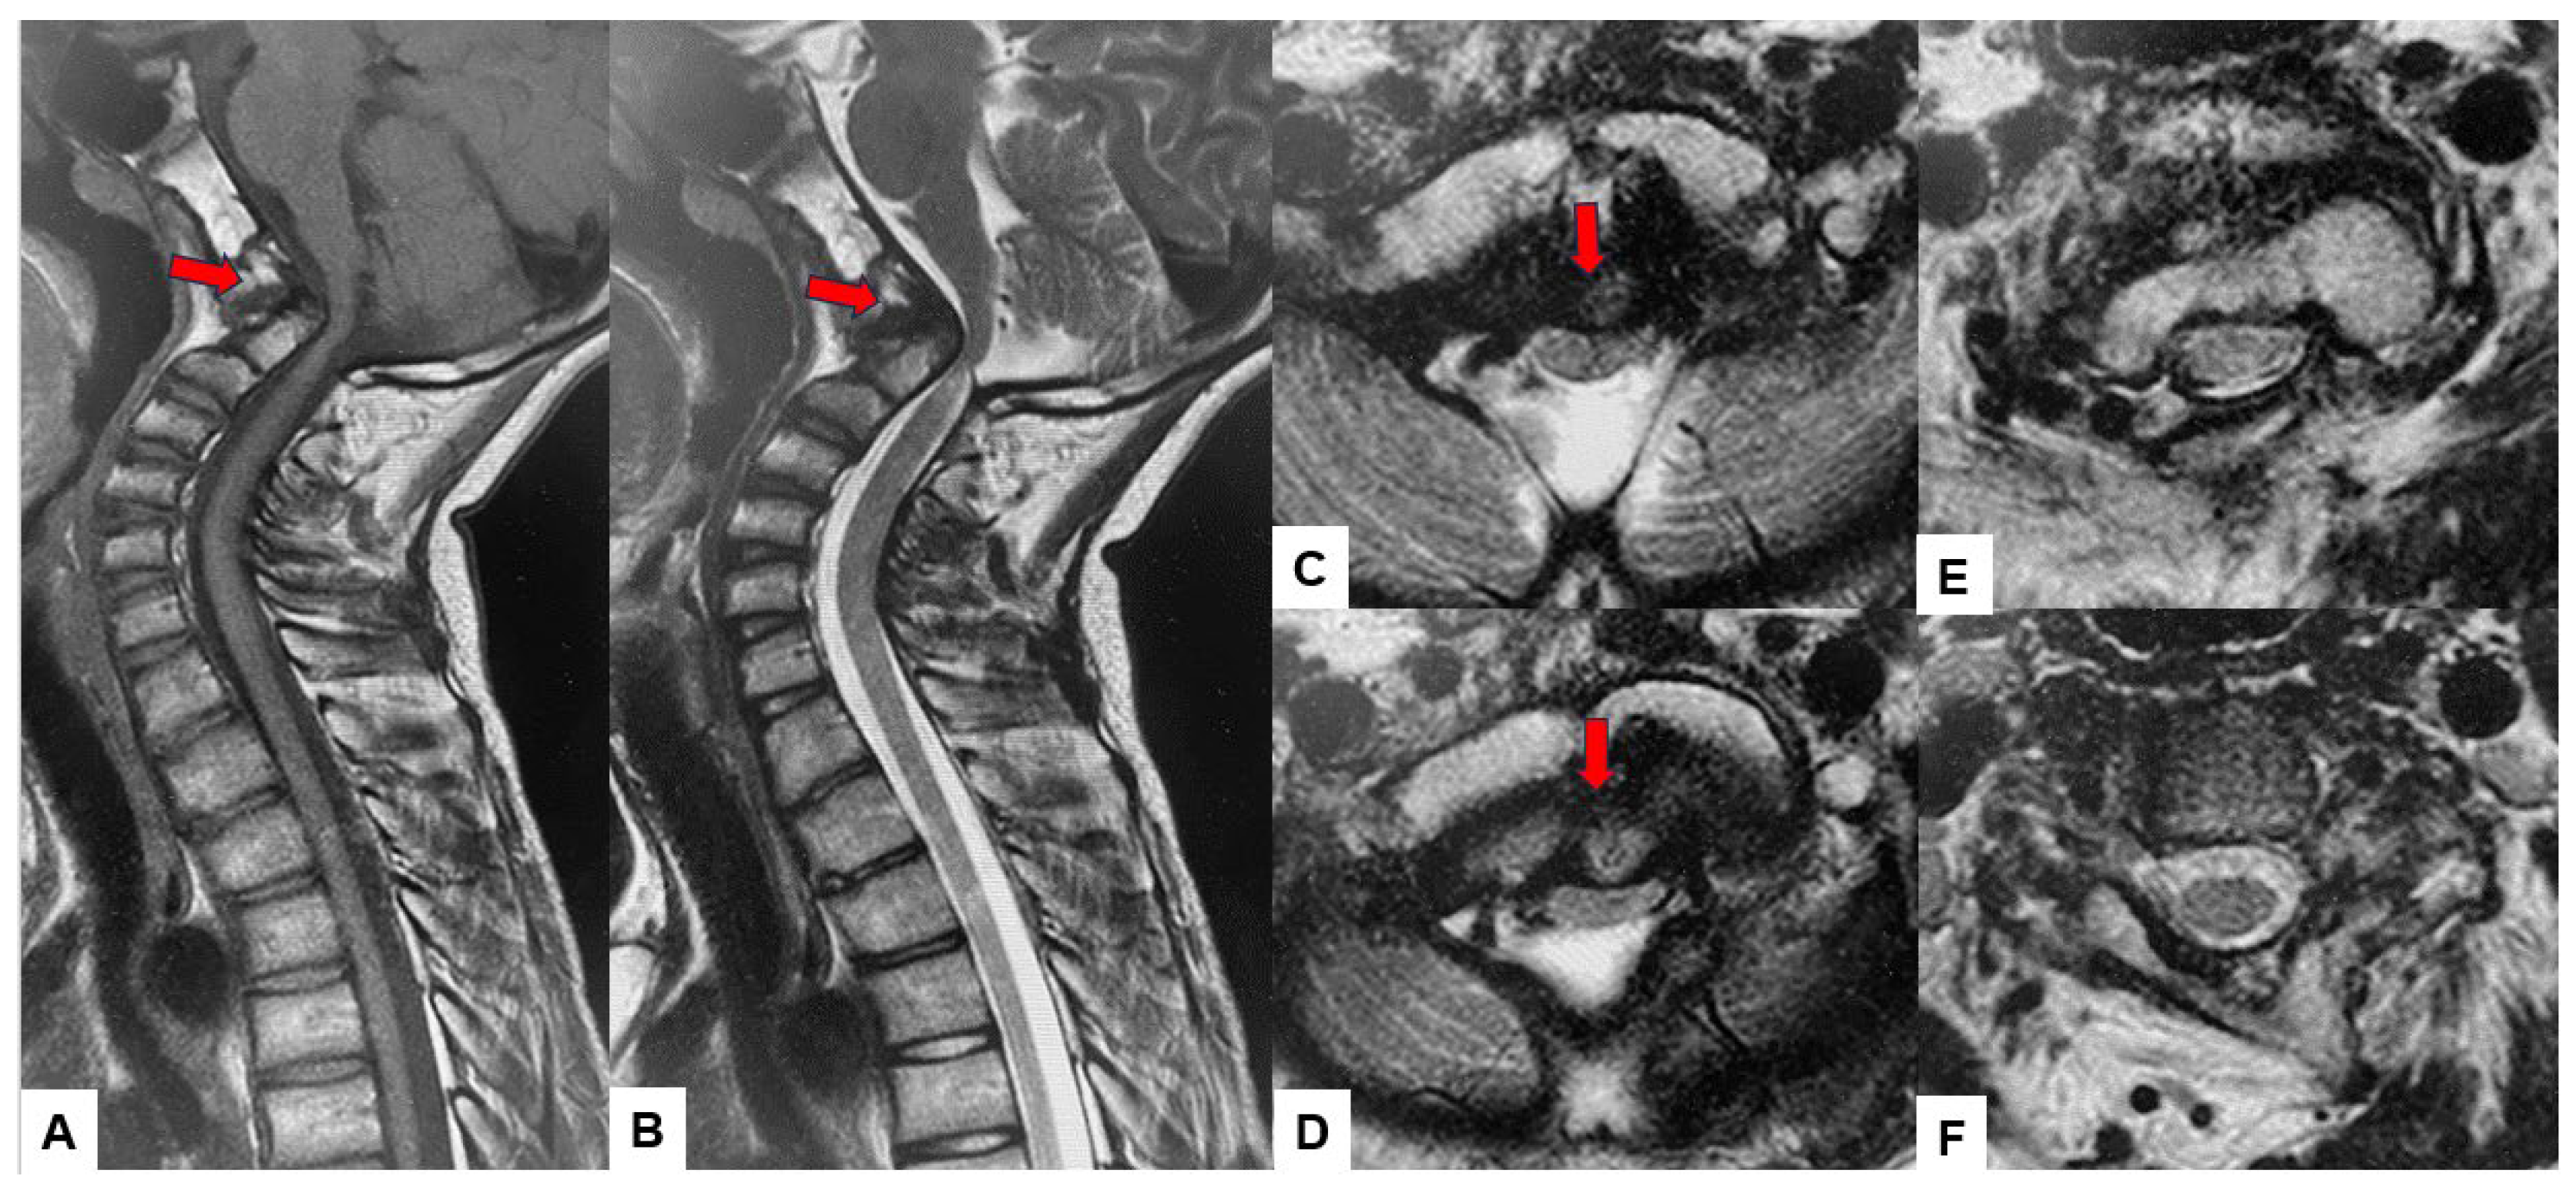

2.3. Preoperative Imaging